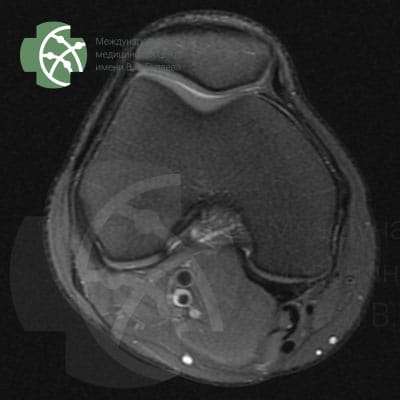

MRI of the knee joint

Magnetic resonance imaging of the knee joint without contrast agent

Our MRI knee joint protocol includes the following sequences:

Program / slice thickness

PD FS saggital 3 mm

T2 saggiati 3 mm

T2 FS saggital 3 mm

PD FS coronal 3 mm

T1 coronal 3 mm

PD FS axial 3 mm

MERGE saggital 3 mm